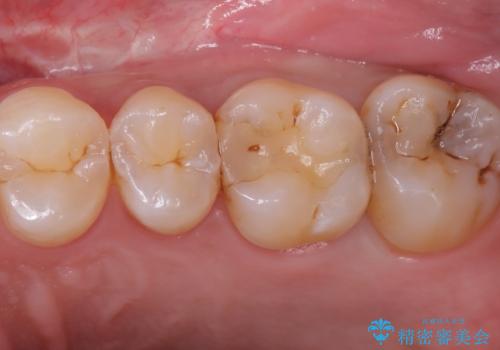

- 元々入っていたセラミックインレーは、6番目と7番目の歯の隙間を無理やり咬合面の近遠心的幅径を伸ばし埋めたような形態で、下部鼓形空隙が広めで食渣が溜まりやすい状態でした。

セラミックインレーを除去したところ、残存歯質が少なく破折のリスクを説明し、オールセラミッククラウン(スタンダード)でのやり替えとなりました。